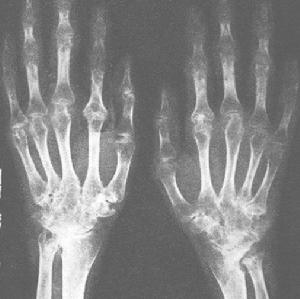

光鏡檢查信息本病腎小球變化最顯著,石蠟切片顯示腎小球髒層上皮細胞擴大,細胞內空泡形成空泡通常小而均一故細胞呈蜂窩狀,胞漿幾乎消失而不宜辨認壁層上皮細胞受累相對少見,內皮細胞和系膜細胞偶可見到空泡。在早期或較輕的患者,腎小球可無其他異常,隨著病情進展至腎功能衰竭,逐漸進展至腎小球節段性或全球性硬化在硬化小球仍能發現有空泡形成的細胞,為進展性腎病患者的診斷提供了線索腎小管有相似空泡細胞以遠曲小管和亨勒(Henle)襻最為明顯。近曲小管細胞較少受累。動脈及小動脈中有大量空泡細胞。內皮細胞常受累細胞擴大呈泡沫狀。血管中層平滑肌細胞內有大小不等的空泡。

鋨固定塑膠包埋組織切片用甲苯胺或亞甲藍處理後,可在先前提到的細胞內包涵體的相應部位見到細的暗染的顆粒狀包涵體。這種技術診斷價值更大,尤其是在完全或局灶硬化的腎小球,這種方法也可以用來辨認受累的間質細胞。